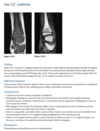

12

A 21-year-old man with worsening pain in the left wrist after an injury 6 months earlier (Fig. 2.13.1).

Figures 2.13.2 and 2.13.3 are of a 46-year-old man with wrist pain

Anteroposterior view of the left wrist

(Fig. 2.13.1) shows an ulna that is shorter than the

radius (i.e., negative ulnar variance or ulnar minus

variance) and a lunate that is sclerotic and some-

what irregular in shape.

Kienböck disease (i.e., lunatomalacia)

Kienböck disease, or lunatomalacia, is

osteonecrosis of the lunate. It is most common in

­ patients 20 to 40 years old and has a predilection

for the dominant hand in individuals involved

in manual labor.

Cause unknown

shortened ulna

in relation to the radius (i.e., negative ulnar variance

or ulnar minus variance) is seen in up to 75% of pa-

tients with lunatomalacia and is considered a major

cause of the disorder

The imaging findings, which do not always corre-

late with the patient’s symptoms, include increased

density or sclerosis of the lunate and, eventually, alteration in the normal bony shape with collapse

on radiographs.

For example, in a 46-year-old

man with wrist pain, a coronal T1-weighted image

(Fig. 2.13.2) demonstrates low signal intensity in

the lunate (arrow) and negative ulnar variance. The

gradient-recalled echo MR image (Fig. 2.13.3) shows

the signal intensity within the lunate to remain low

(arrow). These features are diagnostic of osteone-

crosis (i.e., Kienböck disease). Surgical intervention

includes lunate replacement, radial shortening, and

ulnar lengthening.